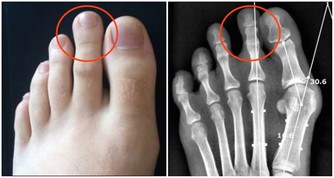

3.遺傳因素:

國內外許多研究都證明,老年癡呆患者的後代有更多機會患上此病。但是,其遺傳方式目前仍不清楚。有人認為是顯性基因遺傳;有人則認為是隱性基因遺傳;也有人認為是多基因常染色體隱性遺傳,且遺傳作用可受環境因素和遺傳因子的突變所製約,以致中斷其遺傳作用。也有一些研究認為老年呆屬非遺傳性疾病,如血管性癡呆與遺傳無直接關係。